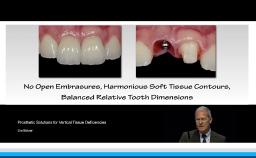

The lecture reviews the digital possibilities to design esthetics and thereby control the esthetic outcome in implant dentistry. The presentation begins with a discussion of the most frequently used criteria to define treatment success in implant dentistry. Clinical cases demonstrate how digital technologies allow planning in three dimensions for optimal esthetics. Practical methods to measure esthetic outcomes are also provided, based on four parameters: implant placement, soft tissue management, prosthetic considerations, and patient satisfaction.

- recognize the ideal abutment design for soft tissue esthetics using CAD/CAM technology